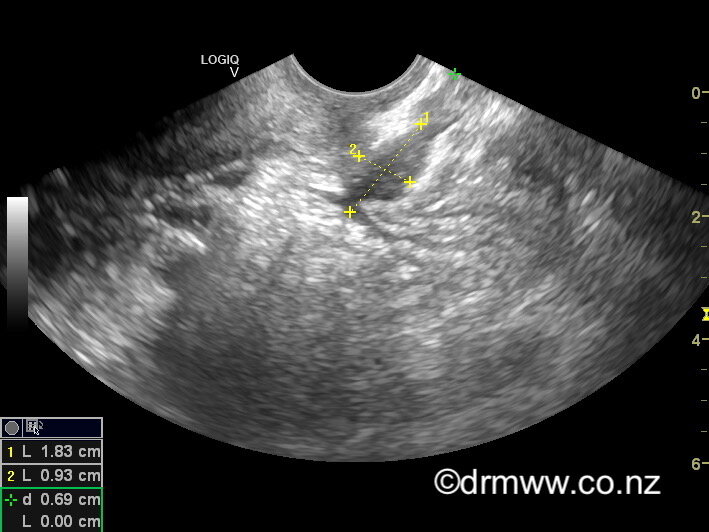

Endometriosis tissue will typically grow in areas deep in the pelvis, such as behind the uterus, between the vagina and rectum (Pouch of Douglas), in the rectum, the ovaries, and the bladder. Deep infiltrating endometriosis is the definition given to endometriosis that has invaded at least 5mm deep into the tissue. Often, it is only the most experienced practitioners who can spot these areas of deep endometriosis when they position the ultrasound probe up against the diseased regions, through the back of the vagina. The areas of endometriosis appear as darker patches as they are denser with the scar tissue they contain. Because Dr Wynn-Williams performs surgery and excises endometriosis without delay - often only a few days after he has completed the ultrasound scan - he is continuously improving his skill in recognising lesions of deep infiltrating endometriosis.

A rectal muscularis endometriosis lesion seen on TVUS

Endometriosis tissue that grows in the bowel (rectum, sigmoid, and sometimes the caecum) will often cause symptoms such as painful bowel motions (dyschezia), rectal bleeding, constipation, diarrhoea, and long skinny bowel motions (ribbon stools). In practised hands, bowel lesions can be seen quite clearly using TVUS. The ultrasound allows Dr Wynn-Williams to work out the size and number of bowel lesions present and give you several options for how to manage your symptoms. If you have nodules in the bowel that are larger than 3cm or multiple areas of bowel endometriosis, you may be referred to a colorectal surgeon as part of your management plan. The majority of lesions will be smaller than 3cm and will be managed by Dr Wynn-Williams himself. If the extent of the endometriosis in the bowel or bladder is seen to be extensive, then you may be referred for an MRI scan. Endometriosis on the small intestine cannot be seen on TVUS.